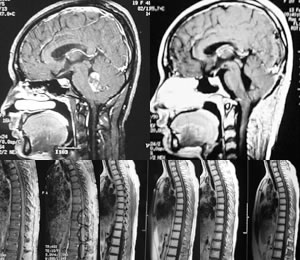

张某某,女,19岁,2002年11月13日因“头痛1月余”就诊,磁共振成像(MRI)示小脑蚓部及第四脑室异常增强团块信号影(图1)。给予开颅手术治疗,病理示髓母细胞瘤。术后复查MRI示增强信号影消失(图2)。术后予放疗,全脑34 Gy/17 f,脊髓35 Gy/20 f。2002年12月3日至2003年1月23日补充小脑放疗(20 Gy/10 f)。

2005年复查MRI,发现肿瘤发生胸腰骶段转移(图3),给予调强放疗,总量30 Gy,2 f/d,1 Gy/f,3周。从2005年6月到2006年2月共使用TMZ 7个周期,2005年10月肿瘤达CR,强信号影消失(图4)。

图1 术前MRI示小脑蚓部及第四脑室异常增强团块信号影

图2 术后MRI示增强信号影消失

图3 MRI示肿瘤复发,发生胸腰骶段转移

图4 使用TMZ 7个周期后,肿瘤达CR,强信号影消失

图5 放疗+化疗巩固治疗有效,异常增强信号未再出现, 百拇医药